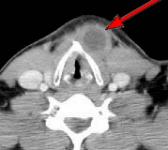

Fig.1 Fig.2 Fig.3 Fig.4

CLINICAL PRESENTATION: This patient presented with a mid-line and left paramidline mobile neck mass and was referred to AIC for a helical CT scan of the neck soft tissues.

HELICAL CT FINDINGS: The CT scan was performed on AIC’s Multi-slice, Multi-detector Helical CT Scanner with 2.7 mm axial sections at 2.5 mm intervals before and during infusion of low-osmolar, non-ionic contrast using a power injector. It shows a lobulated cystic mass (arrows) in the neck at and below the hyoid bone in the midline and to the left of it, with portions of it behind the hyoid bone and portions embedded in the left strap muscle.